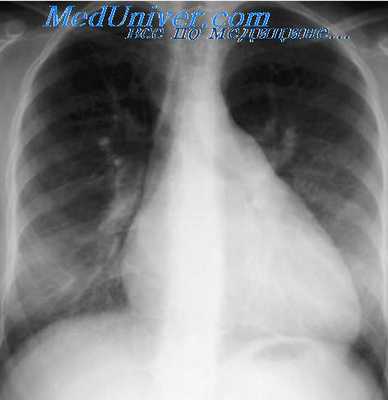

Рентгенография органов грудной клетки обнаруживает кардиомегалию, явления застоя в малом круге кровообращения. Рентгеноконтрастная вентрикулография, МРТ и МСКТ сердца являются высокоспецифичными методами топической диагностики аневризмы, определения ее размеров, выявления тромбоза ее полости.